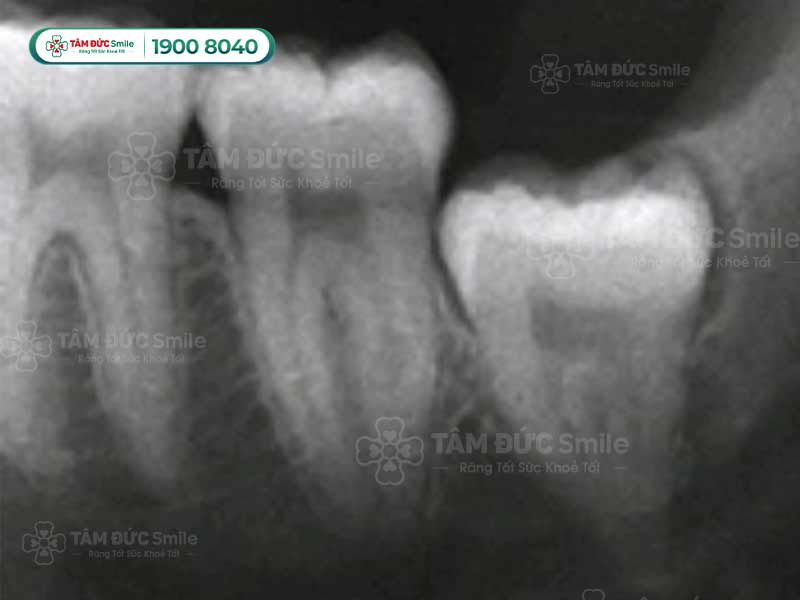

Vị trí và hình dáng của răng khôn

1.2. Răng khôn nằm ở vị trí khuất trong cung hàm

Tính từ ngoài vào trong, răng khôn nằm ở vị trí số 8 trong cùng của hàm. Vị trí này gây khó khăn cho bác sĩ khi phải đưa các dụng cụ nha khoa vào trong như tay khoan, mũi khoan, kìm nhổ răng,...

Đối với những người có cung hàm hẹp thì việc nhổ răng khôn càng khó khăn hơn, dễ làm tổn thương các mô và răng xung quanh. Nhổ răng khôn nguy hiểm còn vì một số người có răng số 8 ngắn, phần lợi phát triển lớn bao trùm răng cũng gây khó khăn cho bác sĩ. Kìm khó kẹp vào răng, kẹp trượt dẫn tới va chạm vào các răng khác rất nguy hiểm.

Răng khôn nằm ở vị trí số 8 trong cùng của hàm